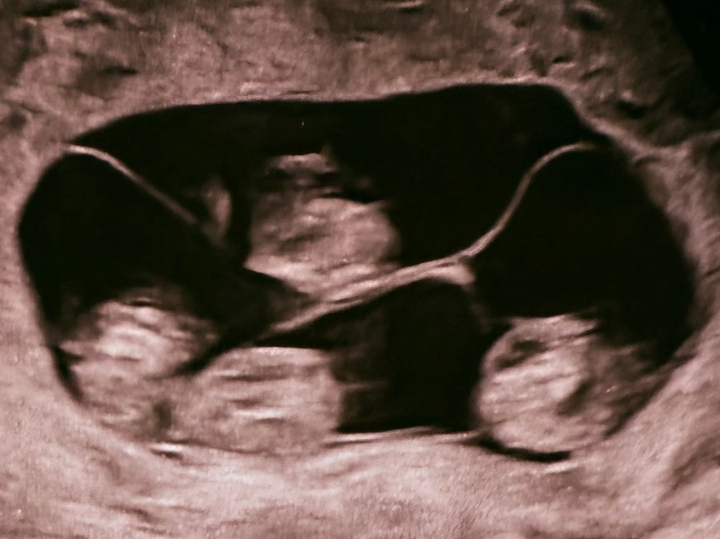

В Санкт-Петербурге зафиксирован редкий случай в акушерской практике: 47-летняя женщина родила четверняшек. Беременность была однояйцевая, поэтому малыши выглядят очень схоже и являются практически «копиями» друг друга. О том, как проходили роды и какие сложности преодолели врачи и мать, читайте в новом материале 5-tv.ru. В Санкт-Петербурге в родильном доме №17 у 47-летней женщины родились четыре девочки при однояйцевой беременности. По данным врачей, речь идет о крайне редком случае монохориальной четверни, когда все дети развиваются в одной плаценте и имеют идентичный генетический набор. Специалисты отмечают, что подобные роды практически не встречаются в медицинской практике: по мировой статистике, вероятность составляет один случай на 15,5 миллиона беременностей. В России такие случаи ранее не фиксировались. Роды проходили с помощью кесарева сечения на 32-й неделе беременности. Решение о досрочном родоразрешении медики приняли из-за повышенных рисков, характерных для многоплодной б

По данным врачей, речь идет о крайне редком случае монохориальной четверни, когда все дети развиваются в одной плаценте и имеют идентичный генетический набор.

Как уточнили в роддоме, вес девочек составил от 1360 до 1640 граммов, рост — от 37 до 41 сантиметра.

«Девочка-1 — 1400 г, 38 см, девочка-2 — 1570 г, 41 см, девочка-3 — 1640 г, 41 см, девочка-4 — 1360 г, 37 см», — следует из врачебного отчета.